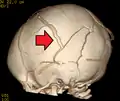

A skull fracture from abusive head trauma in an infant

3D CT reconstruction showing a skull fracture in an infant